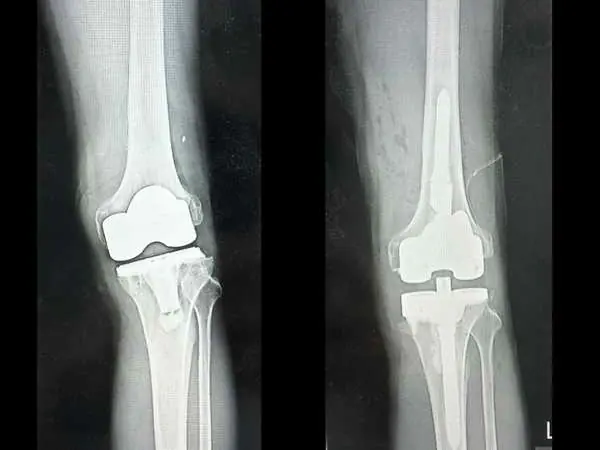

林先生經由親友介紹,轉到台中慈濟醫院趙子鎔醫師門診檢查。X光與電腦斷層顯示,原本置換的人工關節角度出現偏差,導致膝關節軸向錯位、受力不均。

趙醫師表示,人工關節應與人體重心軸線垂直,但病人術後角度卻反向歪了約十度,造成走路一踩就歪,膝蓋反覆發炎積水而疼痛。

趙子鎔醫師與林先生反覆分析溝通後,進行「人工關節翻修再置換」手術,透過電腦斷層影像規劃,重新調整關節角度與力學軸線。

圖二:人工膝關節翻修再置換前(左)與後(右)X光比較。